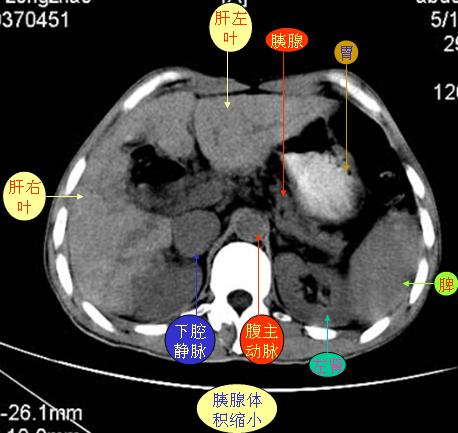

腹部ct解剖与基本病变